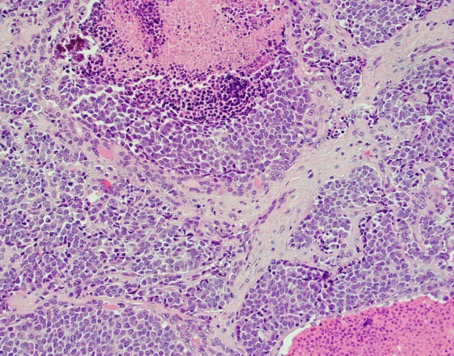

Case history: 17-year-old female with large, solid adnexal mass.

What is the diagnosis?

- Germ cell ...